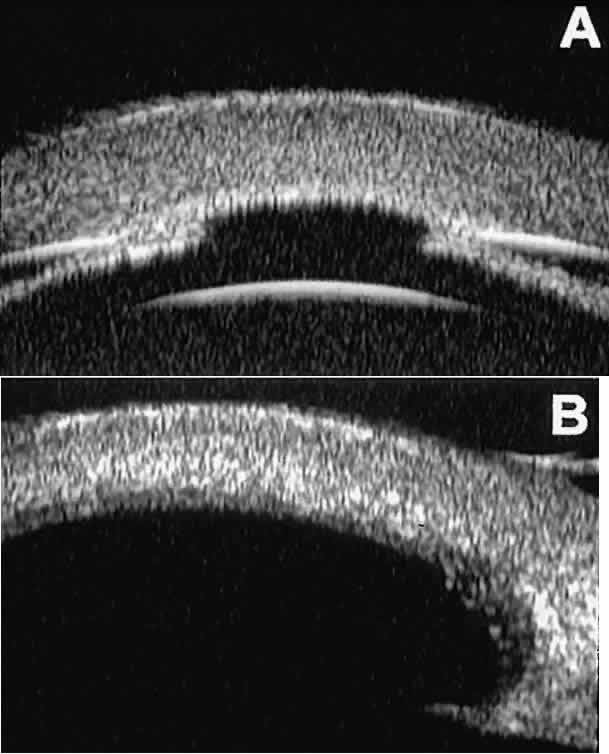

The role of UBM in the preoperative assessment of eyes with cataract is as yet unknown. In certain eyes, however, UBM may reveal features or abnormalities that could alter the ophthalmologist's surgical approach. Postoperatively, UBM can show the size and location of an intraocular lens (IOL) and the positioning of the haptics. A posterior chamber IOL appears on UBM as a highly reflective plate (corresponding to the lens optic) in the retropupillary plane with reverberation artifacts behind it (Fig. 17A). In contrast, an anterior chamber IOL appears on UBM as a sonoreflective plate located anterior to the pupillary plane (see Fig. 17B). In most eyes with a posterior chamber IOL, UBM can show whether the haptics are in the capsular bag (Fig. 18A), in the ciliary sulcus (see Fig. 18B), or in some other anatomic location12 (e.g., resting on the peripheral iris or secured with sutures to the sclera). The haptics are easier to locate if they are made of polymethyl-methacrylate than if they are made of proline because the former has a stronger reflectance.

Fig. 17. Composite UBM images of intraocular lenses. A. Posterior chamber IOL. B. Anterior chamber IOL.

Fig. 18 . Localization of posterior chamber IOL haptics by UBM. A. Haptic in capsular bag (arrow). B. Haptic (bright object just behind peripheral iris) in iridociliary sulcus.

Ultrasound biomicroscopy appears to be helpful postoperatively in determining the extent of postoperative complications of cataract surgery such as serous choroidal detachment (see Fig. 13A), iridocapsular adhesion (Fig. 19A), postoperative hyphema (see Fig. 19B), stripping of Descemet's membrane (see Fig. 19C), and wound gaping (see Fig. 19D).

Fig. 19. Complications of cataract surgery revealed by UBM. A. Capsular adhesion to midzone of iris. B. Postoperative hyphema. Clot appears denser than aqueous with suspended blood cells. C. Stripping of Descemet's membrane. D. Wound gape.